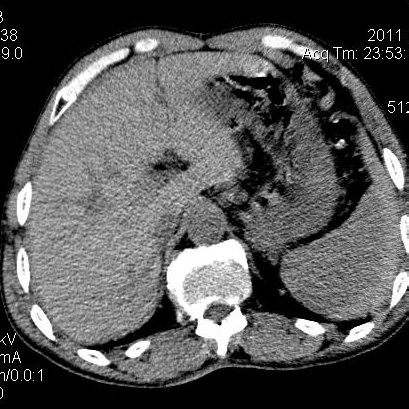

肝左叶发育异常

男性,55岁,骑摩托车摔倒后入院,自述右上腹疼痛

[backcolor=#FF0000]第一次诊断的时候也是这么肯定,可是床旁超声检查并没有发现明显异常,而且患者的一般症状都良好。还好临床只是保守治疗,没有立即手术,第二次复查的时候没有一点变化,又做了MRI检查,没有血肿,

这是一例肝左叶发育异常的,很个性吧~[/backcolor]